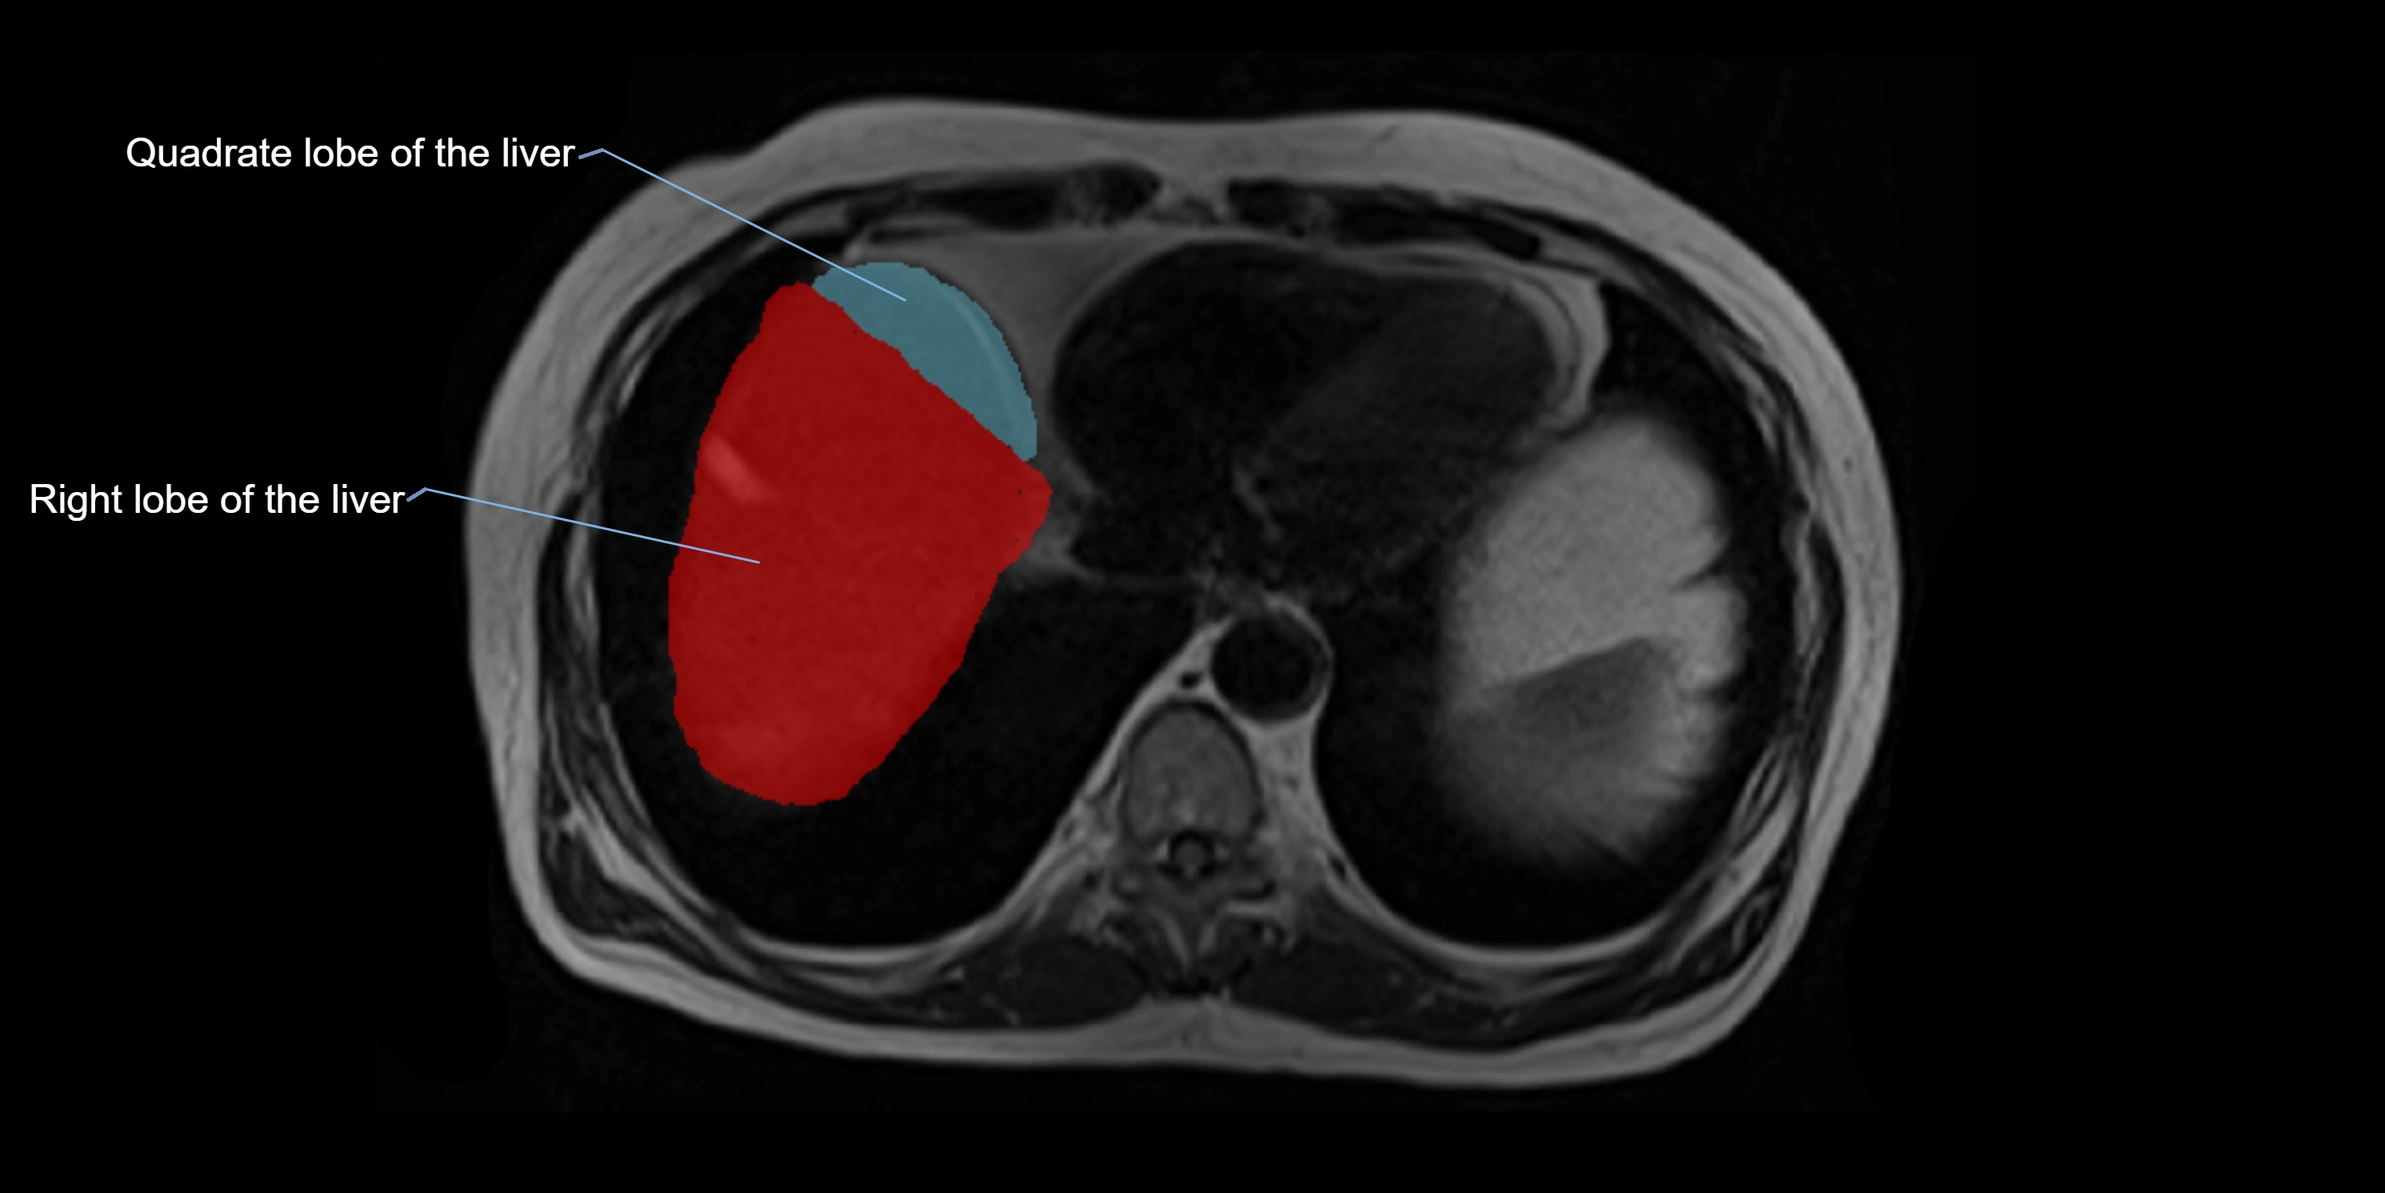

The caudate lobe of the liver is a distinct anatomical subdivision of the liver, designated as segment I in Couinaud’s classification. It lies on the posterior surface of the liver, between the fissure for the ligamentum venosum (left boundary) and the groove for the inferior vena cava (IVC) (right boundary). Superiorly, it is related to the posterior liver surface, and inferiorly it is separated from the left lobe by the porta hepatis.

This anatomical autonomy makes the caudate lobe especially significant in liver surgery, transplantation, and hepatic venous outflow obstruction syndromes (e.g., Budd–Chiari syndrome). Enlargement of the caudate lobe is a characteristic imaging feature in chronic liver disease and cirrhosis.